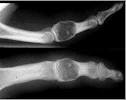

El diagnóstico suele realizarse de manera casual al realizar una radiografía. La imagen radiológica es la de un aumento en la radiotrasparencia del hueso con calcificaciones en el interior de este. La distinción entre lesiones benignas y malignas se realizara mediante estudios radiológicos (los tumores malignos crecen de manera considerable mientras que los benignos no lo hacen), los síntomas del paciente (los tumores malignos suelen doler) y finalmente mediante biopsia del tejido (aunque las diferencias entre las células que componen los tumores malignos y benignos son muy sutiles). Por lo tanto el diagnostico en el caso de los cordomas debe estar siempre apoyado en la clínica y en la radiología, no siendo la biopsia totalmente definitoria.